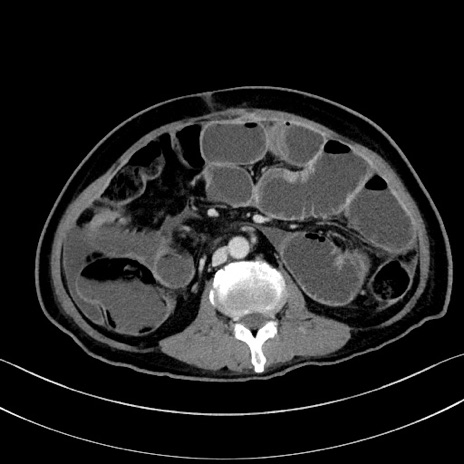

冠状断像